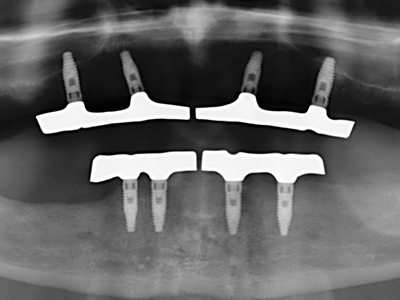

Wie sich in der Vergangenheit gezeigt hat stellt prinzipiell jeder knochenchirurgische Eingriff eine mögliche Indikation für die Piezochirurgie dar. So lässt sich die Präparation des mobilen Segmentes bei der Distraktionsosteogenese (Abb. 23-25) und der Sandwichosteotomie mit speziellen Ansätzen bewerkstelligen, ohne die für den Erfolg beider Techniken essenzielle Blutversorgung des krestalen Anteils zu gefährden (Gonzalez-Garcia, Diniz-Freitas et al. 2008).

Für die Entnahme von Implantaten ist die Präparation eines vestibulären Knochendeckels möglich, der nach Entfernung der Implantatschraube refixiert wird und auf diesem Wege die Kontur des Alveolarfortsatzes erhält.

Weitere Einsatzgebiete ergeben sich in der Kieferhöhlenchirurgie: Hier können nach konzentrischer Präparation eines in der Regel trapezförmigen Knochendeckels der fazialen Kieferhöhlenwand Pathologien und Fremdkörper aus der Kieferhöhle entfernt werden. Der Knochendeckel wird nach Abschluss des intra-antralen Operationsanteils reponiert und durch Verkeilen oder adaptierende Nähte gegen Dislokation gesichert.